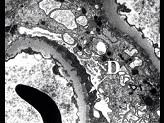

图-1可见上皮下少量嗜复红蛋白沉积(1)(Masson),图-2可见上皮下少量电子致密物沉积沉积(D),上皮细胞足突融合,其病理可诊断为 ( )A...

问题 图-1可见上皮下少量嗜复红蛋白沉积(1)(Masson),图-2可见上皮下少量电子致密物沉积沉积(D),上皮细胞足突融合,其病理可诊断为 ( )

选项 A.Ⅰ期膜性肾病 B.Ⅱ期膜性肾病 C.Ⅲ期膜性肾病 D.Ⅳ期膜性肾病 E.Ⅴ期膜性肾病

答案 A